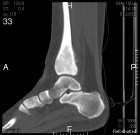

15 year old female complains of ankle pain for three months

Zoom image: Radiological image Radiological image.